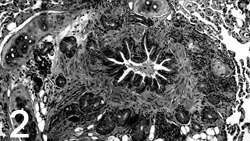

These changes are associated with cellular infiltration of the bronchial mucosa and submucosa. This tissue may also become edematous. See Figures 2 and 3.

F__igure 2. A cross section from the large airway of a cat with asthma, demonstrating the classic findings of smooth muscle hypertrophy,

invagination of epithelium (bronchoconstriction), and luminal exudate.